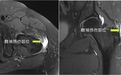

图1 术前MRI

髋袖损伤合并盂唇损伤

目前,国内对髋袖损伤这一疾病相对还认识较少,好多髋袖损伤病人被当作大转子滑囊炎而延误治疗,即使手术治疗也以切开手术较多,不仅手术创伤大、病人疼痛重恢复慢,且不能同时处理合并的关节内病变。

但大家对髋关节外侧疼痛还相对认识较少,常被笼统的称为“大转子滑囊炎”,随着对髋痛的深入研究,应该称为大转子疼痛综合征。其中涉及的转子周围区域的常见病变包括:转子滑囊炎、外源性弹响髋、髋旋转袖损伤三种病变,而且髋旋转袖损伤在其中所见比例接近50%。